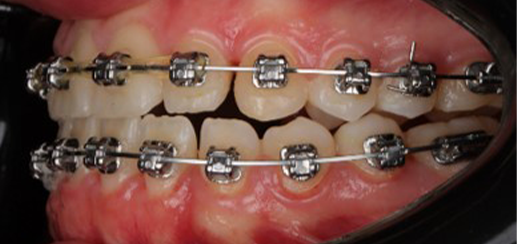

At the end of treatment, the patient’s occlusion was corrected to Class I molar and canine relationships with a physiological overjet and overbite. Irregularities in both arches were eliminated, arch forms were coordinated, and incisor torque was effectively controlled to position the roots centrally within the alveolar bone, enhancing stability. Satisfactory intercuspation was achieved in both the anterior and posterior segments, with maintenance of midline coincidence and periodontal health throughout treatment. The case was finished and transitioned into the retention phase using fixed retainers in the maxillary and mandibular anterior regions.

This case demonstrates that, in the Damon Ultima system, appropriate torque selection provides a rapid and efficient treatment modality, offering enhanced biomechanical control for the clinician and a shorter, more comfortable treatment experience for the patient. In particular, root movements and the finishing phase, which require meticulous management in Class III cases, were completed in a predictable and efficient manner, with high levels of comfort for both the clinician and the patient through the use of carefully selected torque prescriptions.